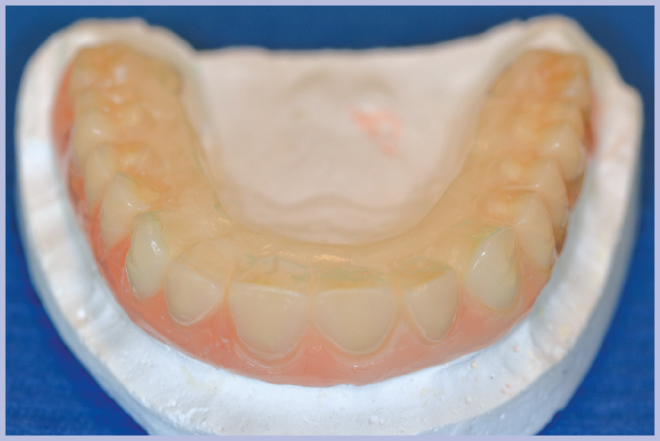

La nuova protesi, realizzata in materiale composito sul modello di quella pre-esistente (Fig. 9), è stata poi ribasata in bocca sull’armatura di rinforzo fissata ai monconi (Fig. 10). Ad indurimento avvenuto della resina per ribasature, si sono rimosse le viti e si è rifinita la protesi. L’operazione di rifinitura da parte del tecnico è di grande importanza, perché si deve il più possibile ridurre l’estensione della flangia vestibolare al fine di favorire una buona detersione da parte del paziente.

- Fig. 9 – Protesi nuova in composito